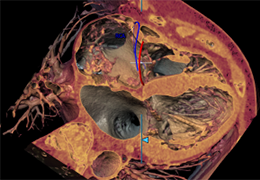

ANYTHINK 经导管主动脉瓣膜置换术分析系统